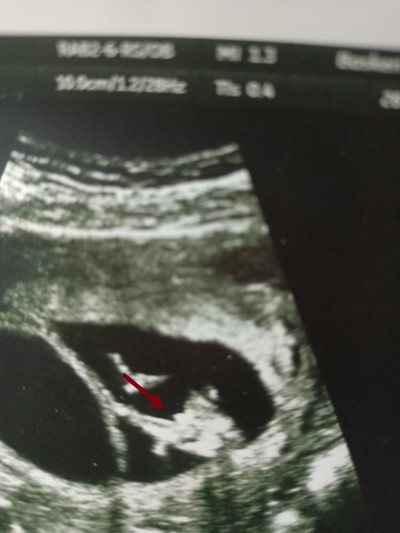

12. Haftamızda çekilen ultrasonumuzda bebeğin p.pisini gördüm dedi. Bu gün tekrar ultrasona girdim 15+3 deyim bebek kız dedi farkli bir doktor. Hangisi yanılıyor olabilir? ( Görüntü bacak arasından çekildi)

Pipi gibi duruyor ama kordon da olabilir

Kız bebeklerin 15 haftaya kadar organı tam seklini almıyor canim şişlik oluyor bi tanidigim da öyleydi kız oldu. En doğru sonuç 15 haftadan sonra belli oluyor.